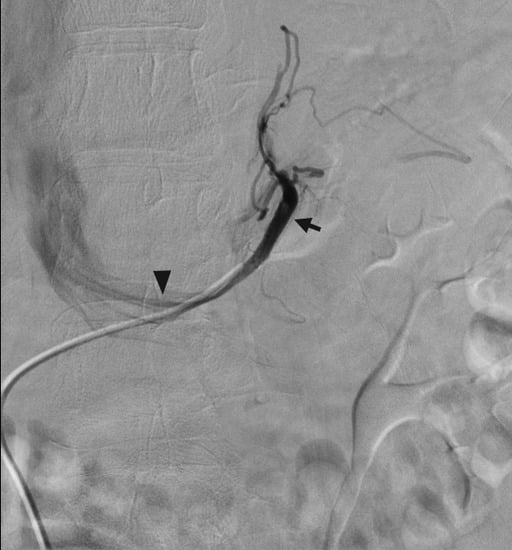

4.3. Parathyroid Hormone Venous Sampling for Primary Hyperparathyroidism

- Taslakian, B.; Trerotola, S.O.; Sacks, B.; Oklu, R.; Deipolyi, A. The essentials of parathyroid hormone venous sampling. Cardiovasc. Interv. Radiol. 2017, 40, 9–21. [Google Scholar] [CrossRef] [PubMed]

- Ogilvie, C.; Brown, P.; Matson, M.; Dacie, J.; Reznek, R.; Britton, K.; Carpenter, R.; Berney, D.; Drake, W.; Jenkins, P. Selective parathyroid venous sampling in patients with complicated hyperparathyroidism. Eur. J. Endocrinol. 2006, 155, 813–821. [Google Scholar] [CrossRef] [PubMed]

- Reidel, M.A.; Schilling, T.; Graf, S.; Hinz, U.; Nawroth, P.; Büchler, M.W.; Weber, T. Localization of hyperfunctioning parathyroid glands by selective venous sampling in reoperation for primary or secondary hyperparathyroidism. Surgery 2006, 140, 907–913. [Google Scholar] [CrossRef] [PubMed]

- Lebastchi, A.H.; Aruny, J.E.; Donovan, P.I.; Quinn, C.E.; Callender, G.G.; Carling, T.; Udelsman, R. Real-time super selective venous sampling in remedial parathyroid surgery. J. Am. Coll. Surg. 2015, 220, 994–1000. [Google Scholar] [CrossRef] [PubMed]